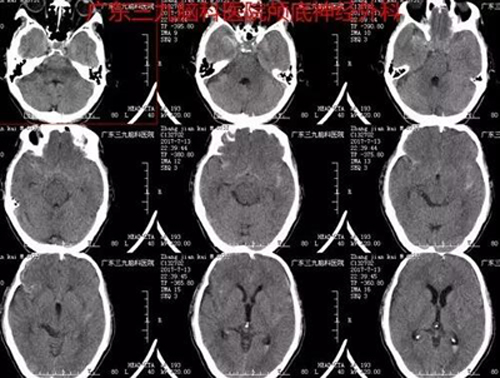

经过头部CT检查发现,张大爷存在蛛网膜下腔出血,血管造影提示动脉瘤。由神经外一科张良主任主刀,行“颅内动脉瘤夹闭术”,术程顺利,术后恢复良好。诊断:右侧大脑中动脉瘤。

图1:术前CT提示蛛网膜下腔出血,脑室系统少量积血